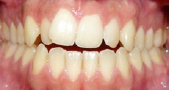

1 Protusión dental

Los dientes superiores sobresalen demasiado, habiendo riesgo de fractura por traumatismo.